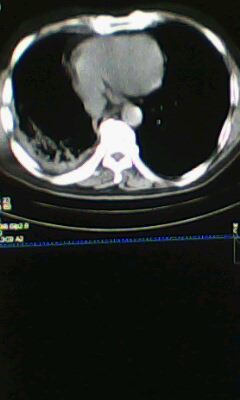

标题: CT25675:男 71 肺癌部分切除术后 3年 [打印本页]

标题: CT25675:男 71 肺癌部分切除术后 3年

1)两肺感染性病变。2)右侧胸膜增厚。3)冠状动脉及主动脉钙化。

1.右肺符合肿瘤切除术后ct表现。

术后改变,双肺内纤维索条影考虑与放疗有关。